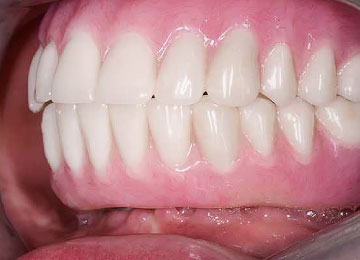

Имплантация зубов: фото «До» и «После»

Фото ПОСЛЕ

Наведите для просмотра

All-on-4